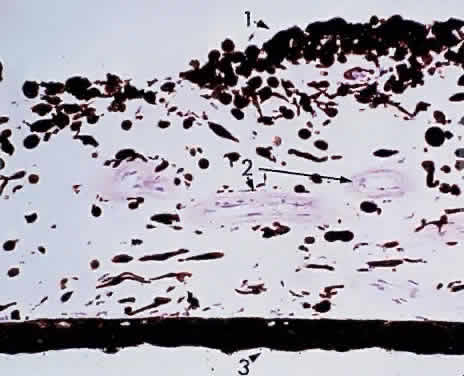

Grossly, the iris appears as a ridged diaphragm, measuring about 12 mm in diameter and 0.5 mm in thickness, with a 3-mm, slightly nasal, off-center pupillary aperture in the resting state. The iris is thickest near the collarette and thinnest at the iris root. Therefore, after blunt trauma, the hyphema that occurs usually is due to a tear at the thin iris root: a traumatic iridodialysis. The degree of pigmentation of the iris determines the color of the eye (Fig. 3). The iris appears blue when the stroma is lightly pigmented and brown when the iris stroma is heavily pigmented. Thus, the assessment of “beauty” in eye color is merely an accident of chromatophore (pigment-bearing cell) collection. A portion of the iris in one eye may be heavily pigmented (brown) and the remainder of the iris lightly pigmented (blue). Thus, one eye alone may show color variations, or one eye may be totally blue and the other eye brown (heterochromia iridium).

Fig. 3. Brown iris. 1, Anterior dense surface pigmentation;2, thick-walled blood vessel; 3, pigmented epithelium (80% of× 195, KEI 8982B).